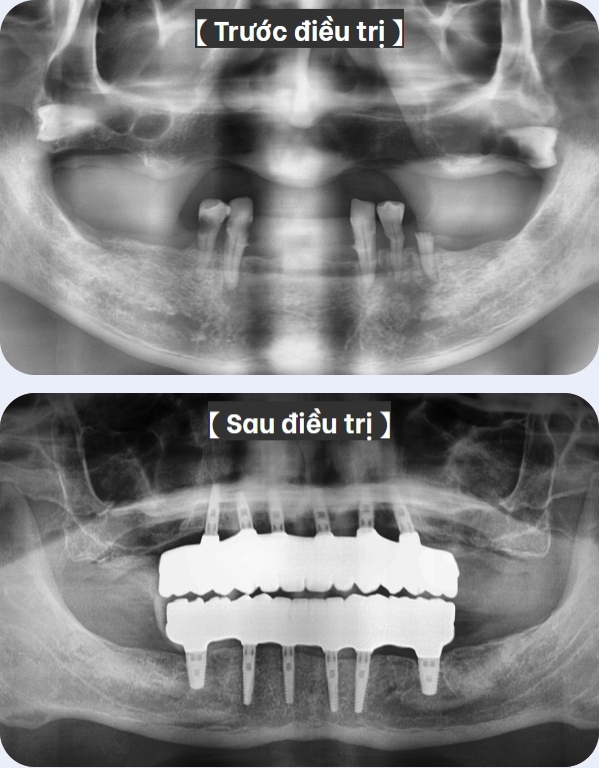

Các trường hợp cấy ghép Implant kỹ thuật số

toàn hàm chắc khỏe và đơn giản

Các tường hợp điều trị cấy ghép Implant

kỹ thuật số toàn hàm tự nhiên